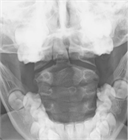

1. 乳児期に認められる頚部腫瘤が、エコー上胸鎖乳突筋の腫脹として捉えられ、正常の筋に認められる層状の筋内部エコー像に乱れが生じている場合には、筋性斜頚と診断する。

1. 一般に筋性斜頚は乳児期に診断されるが、その時期に診断されずに年長で斜頚位を呈している場合には、ときとして診断に難渋することがある。こういった場合には、胸鎖乳突筋の拘縮を触知できない場合でもエコー像では左右差を認めることが多く、診断に有用である。